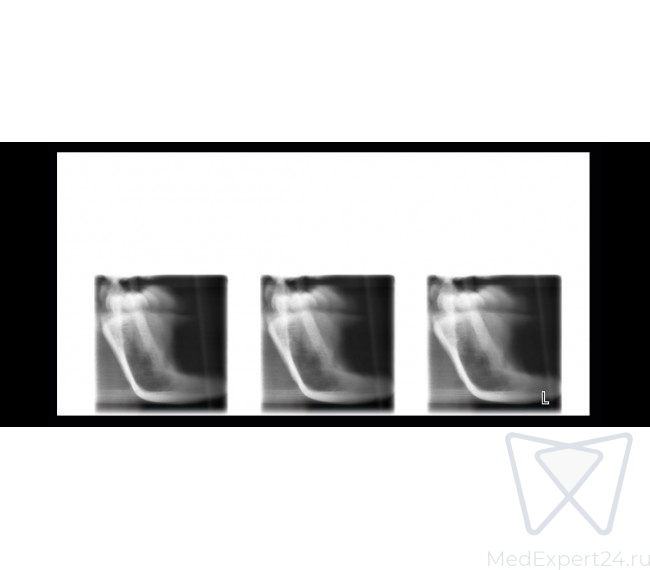

- Боковая и двойная ВНЧС программа,

- Задне-передняя двойная ВНЧС программа,

- Боковой ВНЧС

- Задне-передний ВНЧС

- Боковой задне-передний ВНЧС